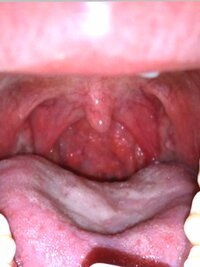

風邪 喉 痛い